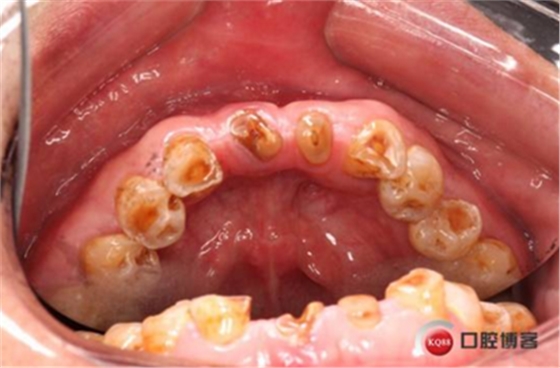

患者,男性,47歲,全身情況良好,無手術(shù)禁忌,口內(nèi)因下前牙缺損松動(dòng)不美觀來院。初診檢查時(shí)發(fā)現(xiàn)患者前牙深覆合,下頜32、42缺失。31、41松動(dòng)二度,切緣磨耗嚴(yán)重,可探及髓腔,無保留價(jià)值。X-RAY檢查顯示:下頜前牙區(qū)寬度狹窄,咬合空間不足,無法行常規(guī)種植修復(fù).

下圖是術(shù)前資料